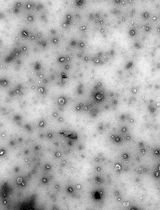

EVs play important roles in health and disease, but their small size, heterogeneity, and variable autofluorescence make analysis challenging [2]. Several techniques have been developed for EV analysis, including electron microscopy, nanoparticle tracking analysis, tunable resistive pulse sensing, western blotting, and ELISA-based assays, each with advantages and limitations [1]. Existing EV isolation protocols, including ultracentrifugation, precipitation, and size-exclusion chromatography, often face challenges such as incomplete removal of contaminating platelets, co-isolation of protein aggregates, variable EV recovery, and loss of vesicles during multiple washing steps [3]. Moreover, differences in centrifugation speeds, buffer preparation, and gating strategies limit reproducibility across laboratories [4]. Flow cytometry–based detection adds further complexity due to EV heterogeneity, variable autofluorescence, and the difficulty of distinguishing true EVs from debris [5].

Bead-based analysis of EVs is commonly used to overcome the challenge of their small size, which limits direct detection by conventional flow cytometry. In this approach, EVs are captured onto larger beads (typically 4–6 μm) coated with antibodies against tetraspanins such as CD63, CD81, or CD9, thereby increasing their effective size and enabling detection and characterization by flow cytometry. Once bound, the bead–EV complexes can be further probed with fluorescent antibodies to analyze additional surface markers and identify subpopulations. While this method is practical and widely accessible, it has important limitations: it selectively enriches only those EVs expressing the capture antigen (e.g., CD63+ vesicles if anti-CD63 beads are used), potentially overlooking other populations, and multiple EVs may attach to a single bead, preventing true single-vesicle resolution. Consequently, bead-based analysis provides useful phenotyping information but does not fully represent the heterogeneity of circulating EVs [6,8].